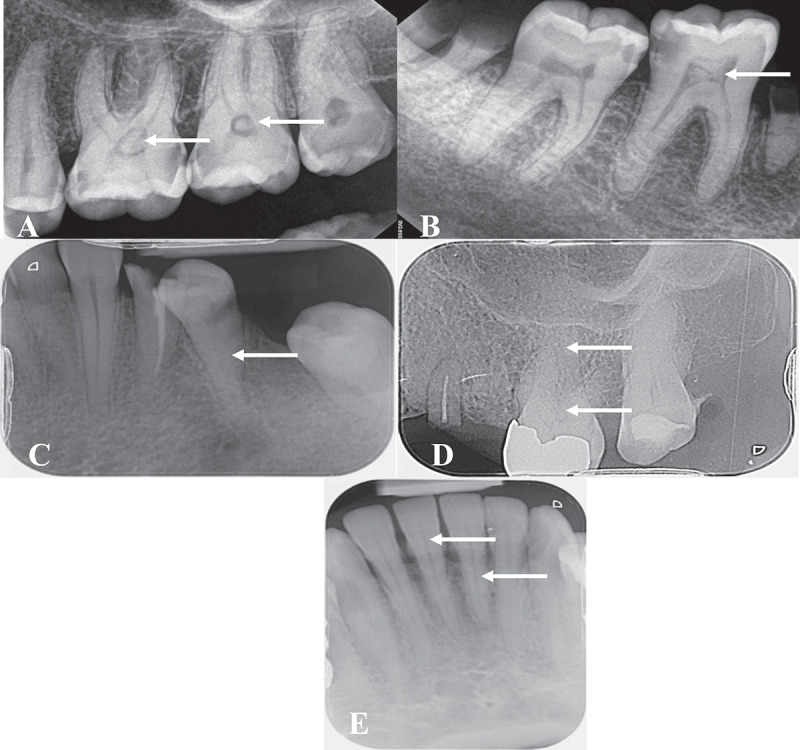

The study aimed to radiographically assess the characteristics of pulp stones (PS) and pulp canal obliteration (PCO) in teeth and examined their associations with various dental parameters such as caries, restorations, periodontal status, and age. This cross-sectional observational study was conducted at the Faculty of Dentistry, King Abdulaziz University between September 2022, and May 2023, involved 101 patients exhibiting 402 teeth with PS or PCO. Data were collected from periapical and bitewing radiographs, and analyzed by two calibrated dentists. Multiple dental parameters were assessed, including caries level, presence and level of restorations, periodontal condition, and age of the patient. The study population consisted of 62 females and 39 males, with an age range of 18-65 years. Inter- and intra-examiner reliability were high (Kappa = 0.88 and 0.98 respectively). PS were more commonly found in molars (81.2%), while PCO were presented in only 115 teeth (23%). Age significantly affected the type of calcification (p < 0.001), with PS more common in the 20-30 age group and PCO more common in individuals over 40. Presence of caries was significantly associated with the type of calcification (p = 0.013), but restoration was not. The majority of teeth with PS (76%) or PCO (93%) had healthy periodontium. Around 40% of teeth with PCO showed signs of periapical changes, a finding significantly different from those with PS (p < 0.001). Pulp calcifications were significantly associated with various dental parameters, including caries presence, age, and periodontal status. The findings provide crucial insights into the epidemiology and aetiology of pulp calcifications.